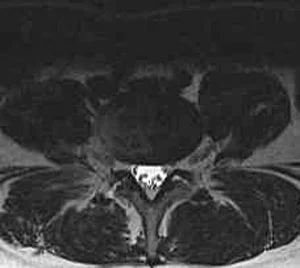

This is a case of a 34 year-old female with progressive low back and right leg pain and weakness. The pain radiated into her right buttock, back of her thigh and calf, and onward towards her heel and outside part of her right foot. She also noted weakness on her right side with the push off phase of walking. She had an MRI that demonstrated an eccentric to the right disc herniation at L5-S1 (Figure 1). Figure 2 demonstrates her normal L4-5 disc level. She had failed non-surgical management in the form of medications, injections, and physical therapy. She ultimately underwent a MLD on the right at L5-S1 with immediate relief of her right leg pain. Figure 3 displays the small surgical incision.